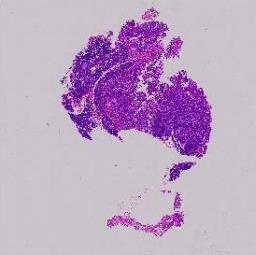

临床资料: 患者:女,年龄:31岁。病史:体检影像学查见胰腺占位性病变,边界清楚。

大体所见: 灰白灰褐色不整形组织一块,体积2.5cm×1.2cm×0.7cm,切面灰白灰褐色,实性,质地中等。